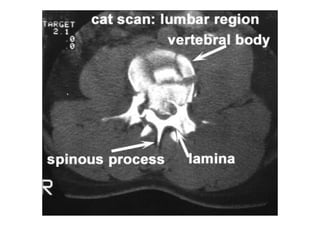

Referência: http://www.accessexcellence.org/RC/VL/

figura